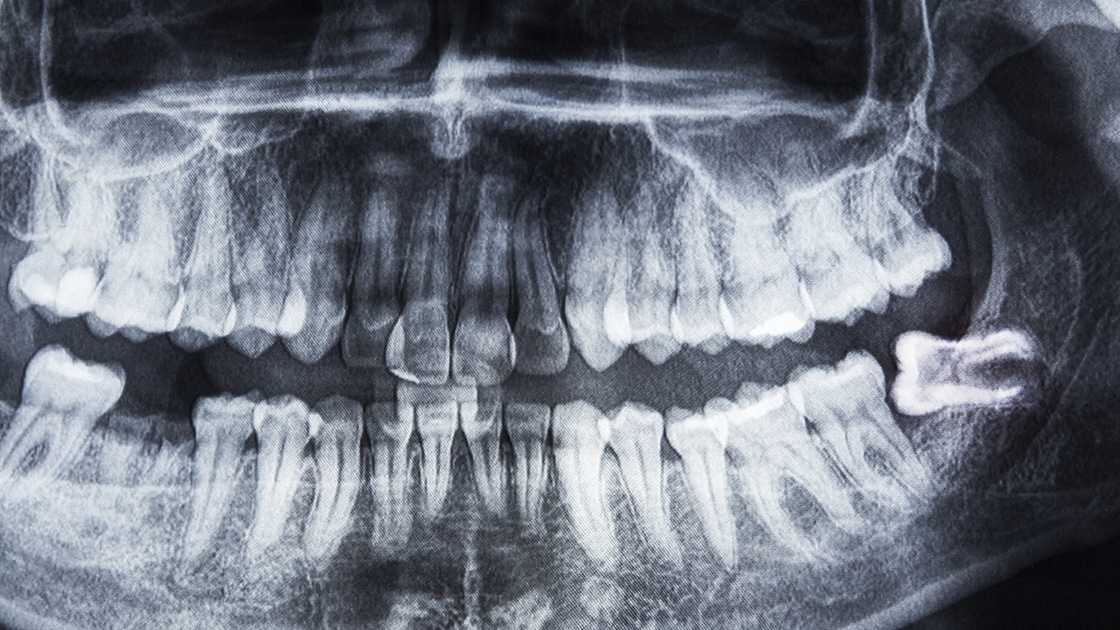

What is Restorative Dentistry?

Restorative dentistry focuses on diagnosing, preventing, and treating oral diseases to repair or replace damaged or missing teeth. It aims to restore your mouth to full function and health while enhancing the appearance of your smile. Whether you have cavities, cracked teeth, or tooth loss, our restorative treatments can rebuild your smile and enhance your overall well-being. We use the latest techniques and materials to ensure your results are durable, comfortable, and natural-looking.